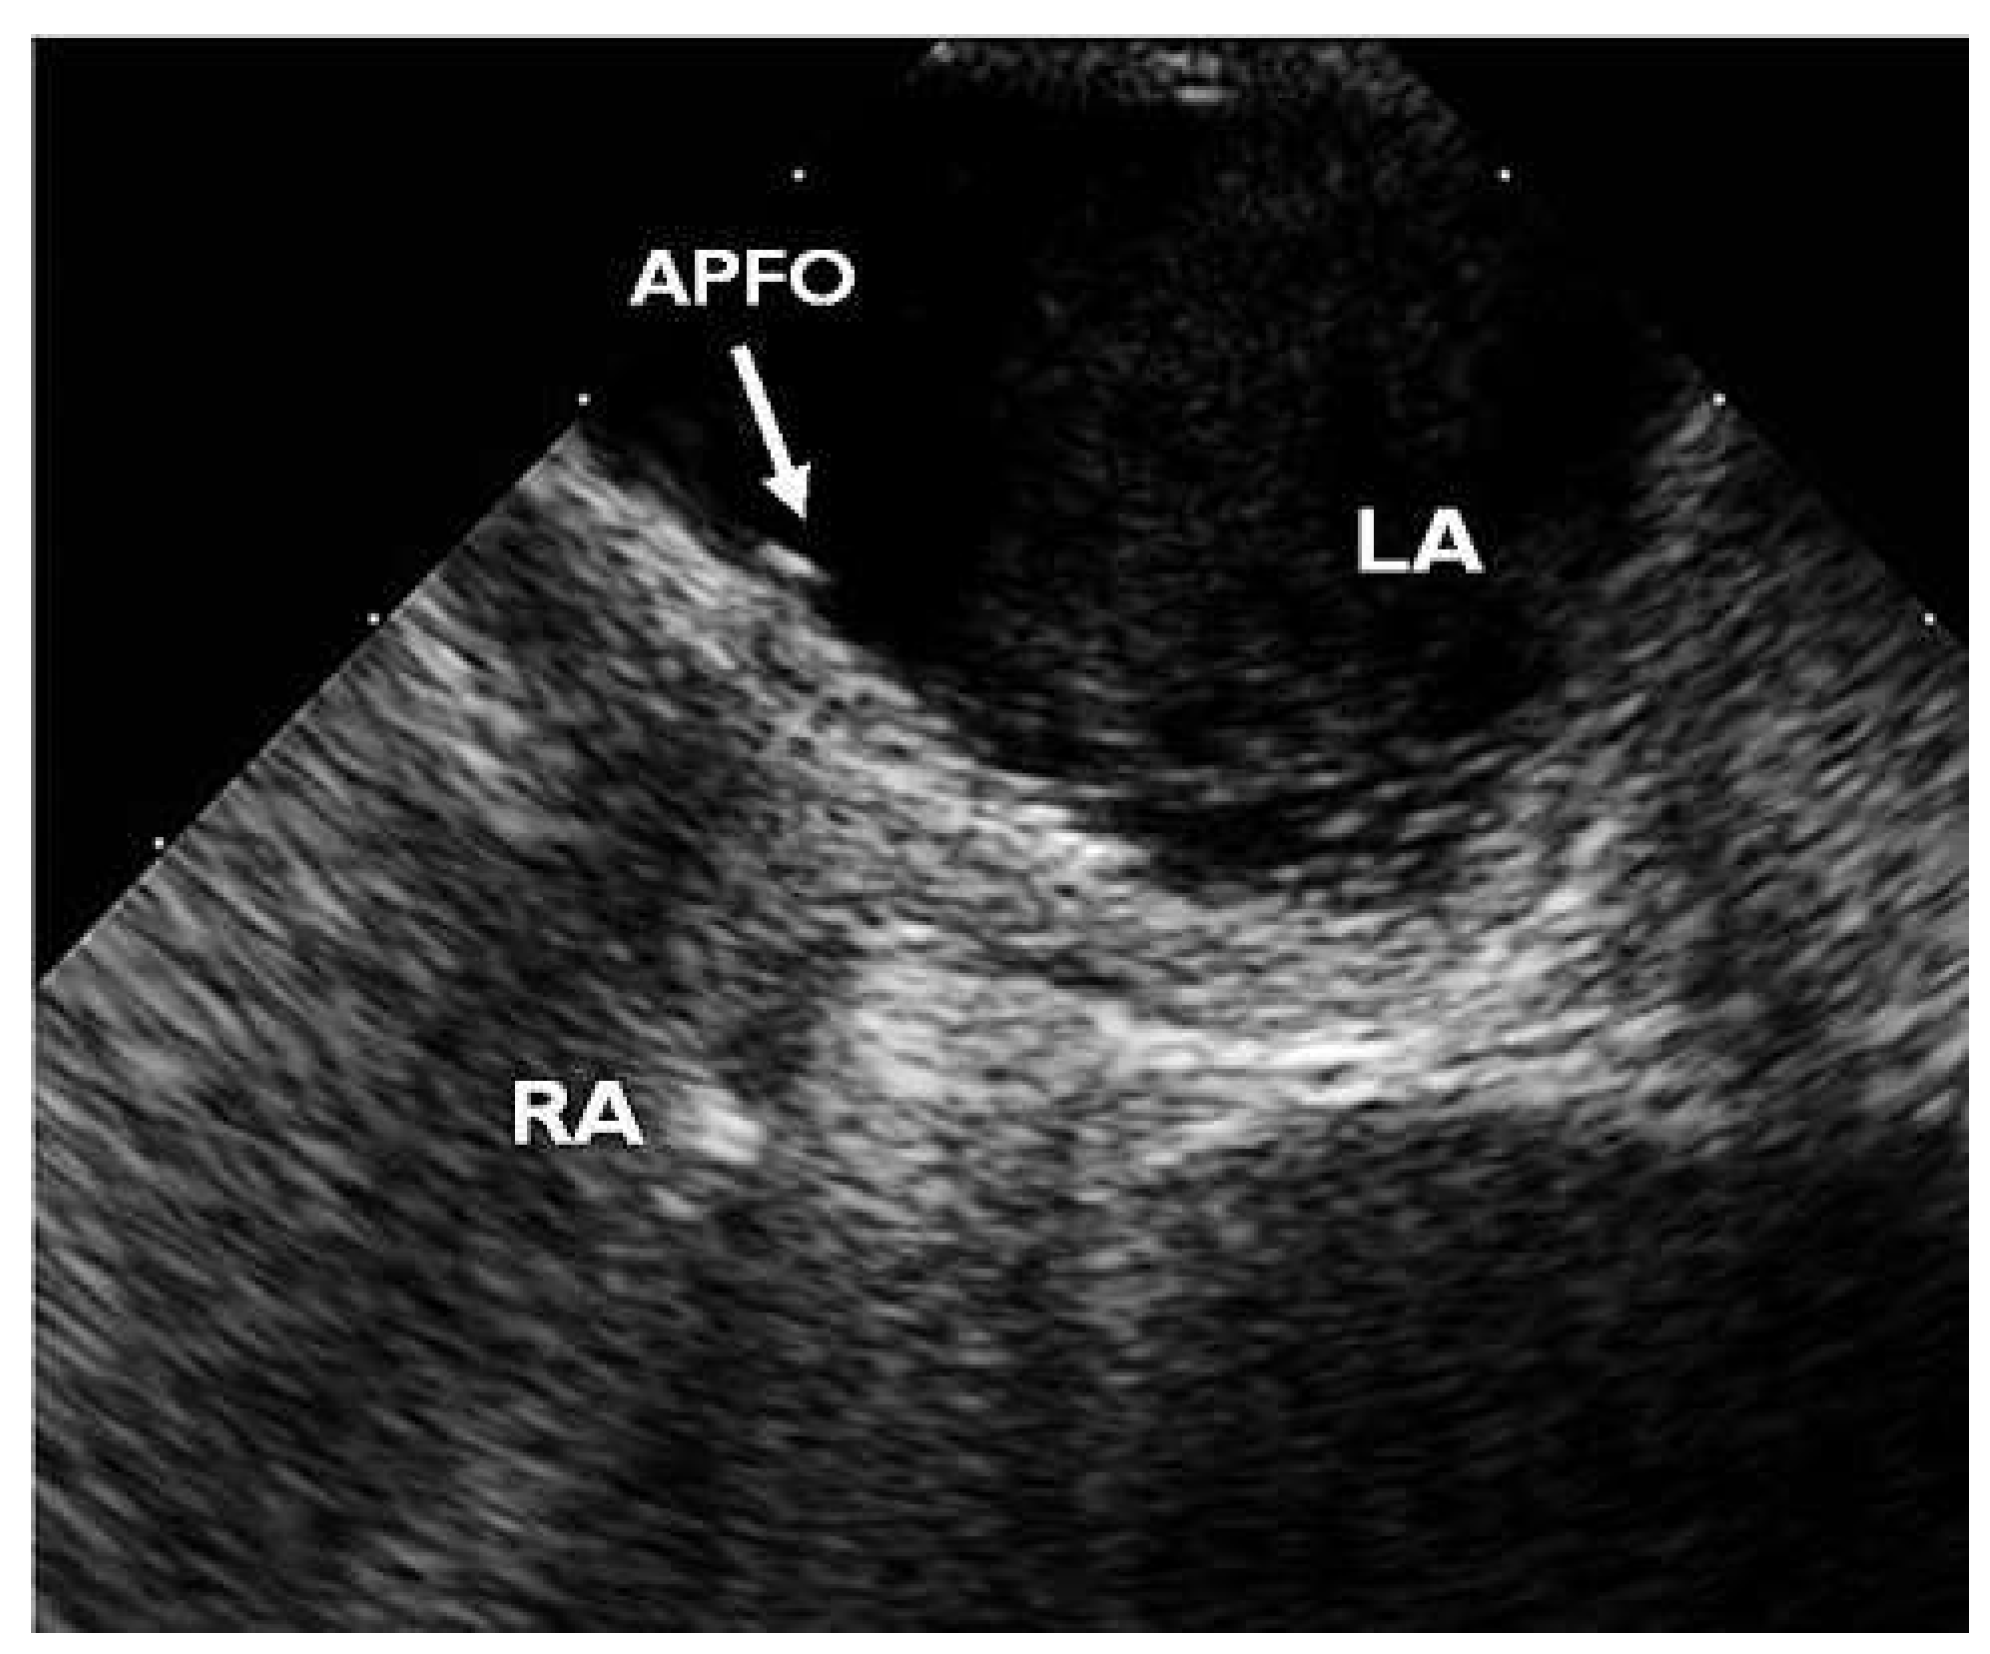

Figure 6. Final contrast TEE showing complete occlusion 6 months after the third intervention. APFO = left disks of first (left) and third (right) PFO Occluders; LA = left atrium; RA = right atrium.

Six months after implantation of the second device, contrast TOE revealed correct position of both devices but a persisting shunt grade II (Figure 4). A third APFO (18-mm) was implanted using the same technique (Figure 5). Contrast TTE at discharge the same day assessed good position of the device without any residual shunt. Clopidogrel 75 mg was again prescribed for 1 month and acetylsalicylic acid 100 mg for 5 months. Six months after implantation of the third device, contrast TOE finally showed complete occlusion (Figure 6) and both platelet inhibitors were stopped.